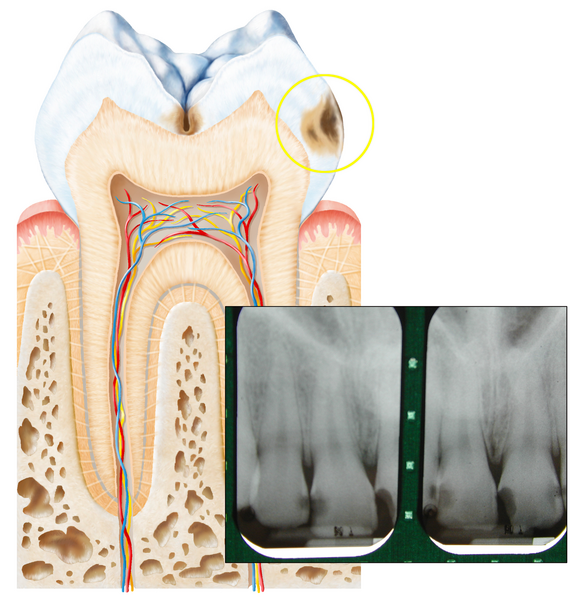

Jetzt entsteht ein Loch

Löcher entstehen oft zwischen den Zähnen. Deshalb sind sie nur auf dem Röntgenbild zu erkennen.